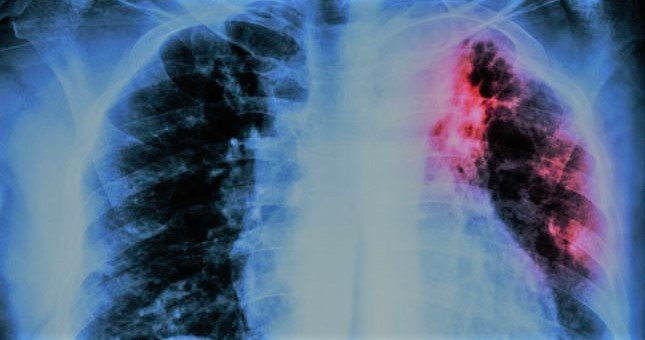

ಬೆಂಗಳೂರು: ಕೊರೋನದಿಂದ ಗುಣಮುಖರಾದವರಲ್ಲಿ ಕ್ಷಯ ರೋಗ ಕಾಣಿಸಿಕೊಳ್ಳುತ್ತಿದ್ದು ಆತಂಕ ಮೂಡಿಸಿದೆ. ಕಳೆದ ಒಂದು ತಿಂಗಳ ಅವಧಿಯಲ್ಲಿ ನಡೆದ ಸಮೀಕ್ಷೆಯಲ್ಲಿ ಈ ಅಂಶ ಬೆಳಕಿಗೆ ಬಂದಿದೆ. ಒಟ್ಟು 225 ಮಂದಿಯಲ್ಲಿ ಕ್ಷಯ ರೋಗ ಕಾಣಿಸಿಕೊಂಡಿದ್ದು ಇವರಲ್ಲಿ 151 ರೋಗಿಗಳು ಇತ್ತೀಚಿಗೆ ಕೊರೋನದಿಂದ ಚೇತರಿಸಿಕೊಂಡವರಾಗಿದ್ದಾರೆ.

ಆರೋಗ್ಯ ಮತ್ತು ಕುಟುಂಬ ಕಲ್ಯಾಣ ಇಲಾಖೆ ಆಗಸ್ಟ್ 16ರಿಂದ ಸೆಪ್ಟೆಂಬರ್ 11ರವರೆಗೆ ರಾಜ್ಯಾದ್ಯಂತ ಮನೆಮನೆ ಸಮೀಕ್ಷೆ ನಡೆಸಿತ್ತು. 151 ಮಂದಿಗೆ ಈ ವರ್ಷದ ಜನವರಿಯಿಂದ ಜೂನ್ ಮಾಸದ ಅಂತ್ಯದ ಒಳಗೆ ಕೋವಿಡ್ ಬಂದಿತ್ತು. ಇದೀಗ ಅವರಲ್ಲಿ ಟಿಬಿ (ಕ್ಷಯ) ರ್ರೋಗ ಕಾಣಿಸಿಕೊಂಡಿದೆ.

ಬೆಂಗಳೂರು ನಗರದಲ್ಲಿ ಅತೀ ಹೆಚ್ಚು 44 ಟಿಬಿ ಪ್ರಕರಣಗಳು ದಾಖಲಾಗಿದೆ. ಉಳಿದಂತೆ ಬಳ್ಳಾರಿ ೨೨, ಮೈಸೂರು 14, ಚಿತ್ರಗುರ್ಗ ಹಾಗು ಕಲಬುರ್ಗಿಯಲ್ಲಿ ತಲಾ 13 ಪ್ರಕರಣಗಳು ಪತ್ತೆಯಾಗಿವೆ.